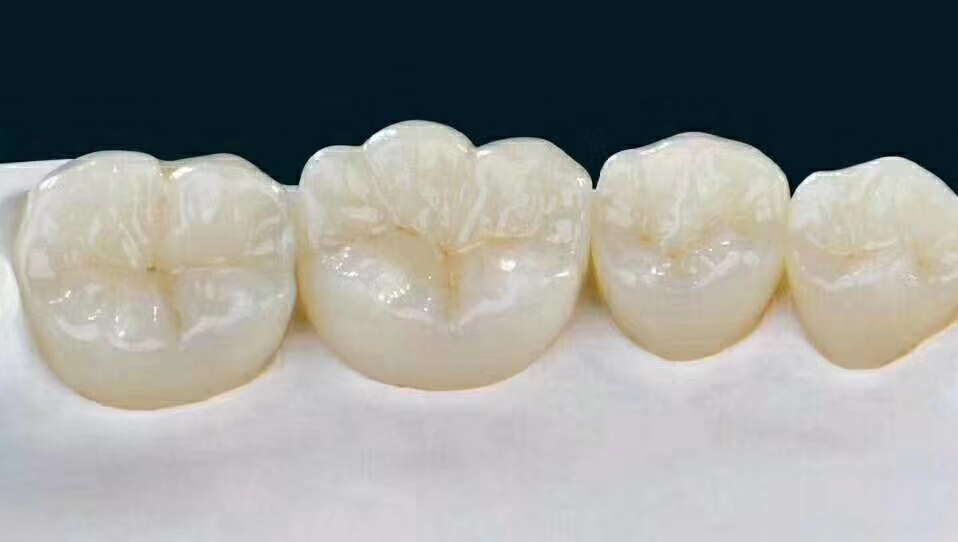

另外需要强调的是,做完根管治疗的牙齿质地比较脆,如果牙齿平时受力较多,或者治疗前因创伤/龋齿造成牙体缺损过多,医生会建议您做一个牙冠将它保护起来。这个就之后再讲了。

根管治疗后需要做牙冠吗?

很多朋友说了:牙齿都不疼了,补好了,为何还要做牙冠呢?

事实上,做完根管治疗后的牙齿,没有了牙髓供给营养,牙齿会变得十分脆弱,剩余的牙齿部分很容易劈裂,下图就是牙医接诊的根治后没做冠的患者,劈裂的牙齿是不是很可怕?

因此根管治疗后一定要做个牙冠将其保护起来。

牙套就是指的烤瓷牙或者全瓷牙:

烤瓷桥